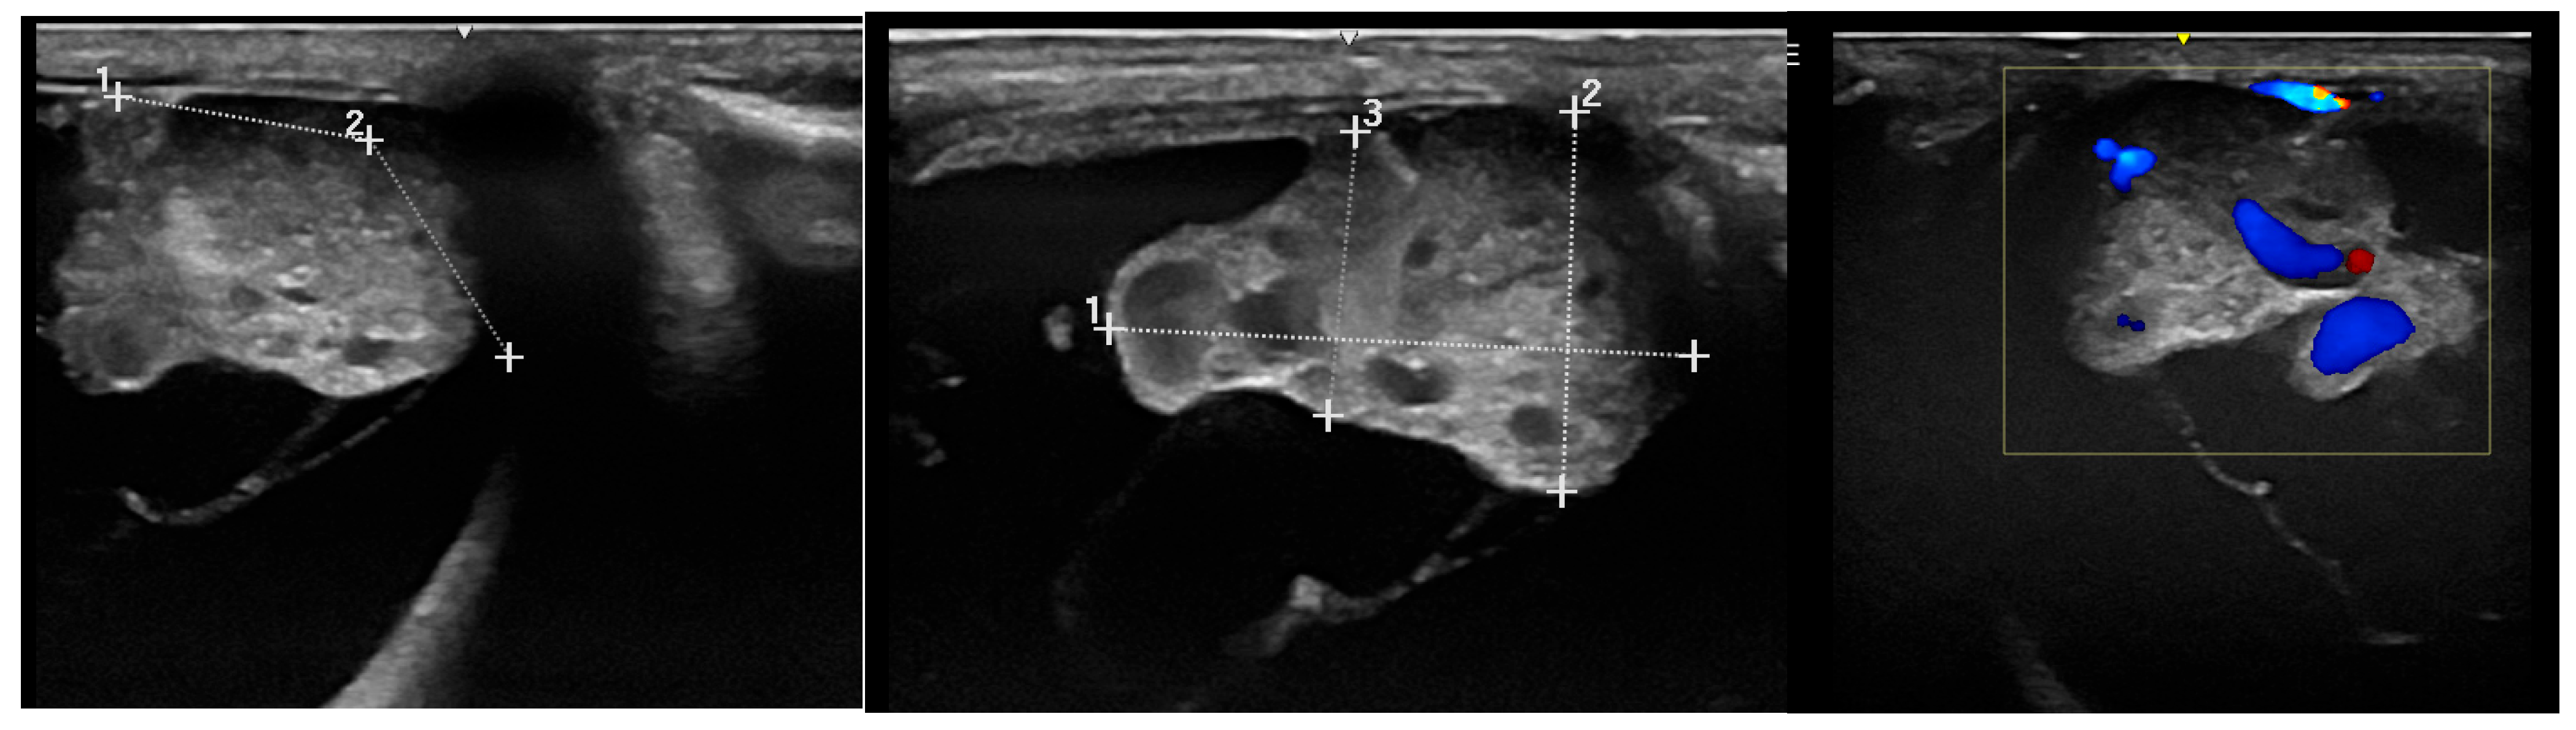

3.2.1. Ultrasonography